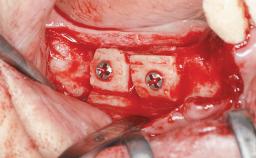

Shell Technique for Horizontal and Vertical Maxillary Bone Augmentation in a Partially Edentulous Patient with Aggressive Periodontal Disease

Bone Augmentation Horizontal|Staged|Vertical

Augmentation Materials Autogenous chips|Autogenous block(s)|Xenogenous

Bone Volume Deficient vertically or deficient vertically AND horizontally